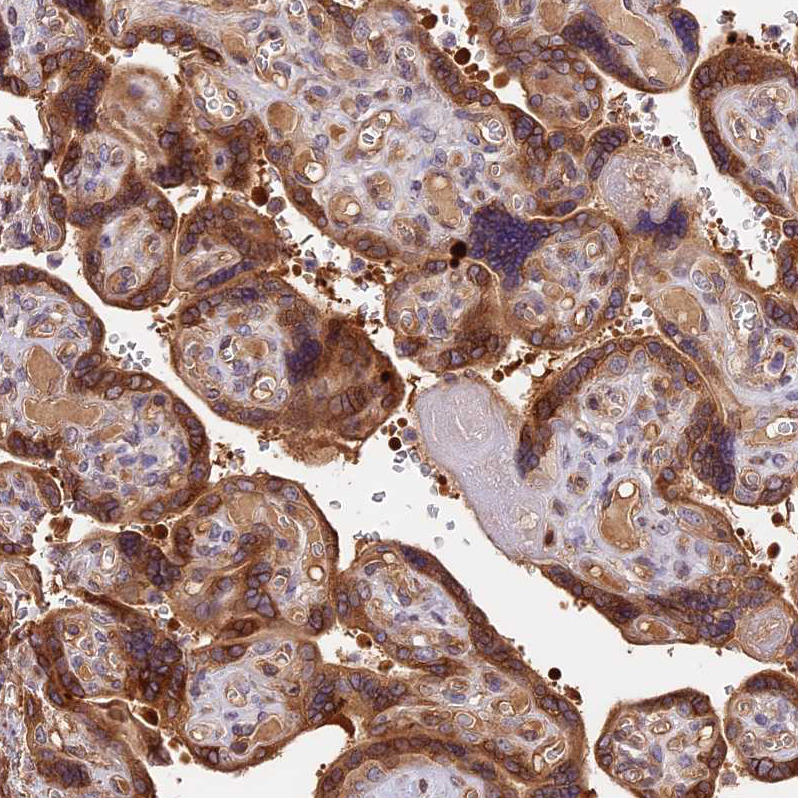

Immunohistochemical staining of human placenta shows strong cytoplasmic positivity in trophoblastic cells.